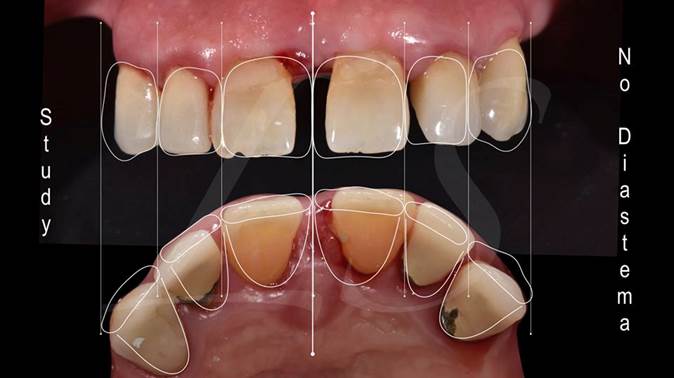

Clinical case: Full-arch implant treatment with immediate loading & extraction implantation

- Courtesy of Dr. Laurent Sers, France -

AnyRidge, R2GATE, guided surgery, Dr. Laurent Sers, immediate loading, maxilla

AnyRidge implant system, R2GATE, Digital prosthesis

“Patient’s smile was recovered on the day of surgery

with reliable & highly-aesthetic results using AnyRidge & R2GATE. ”